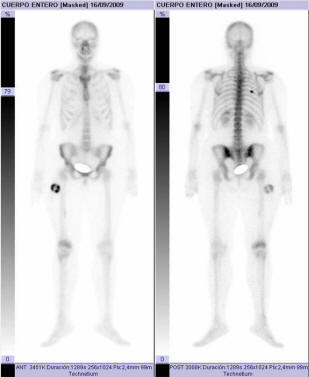

Cuando un médico trata a un paciente el primer paso es evaluar sus síntomas y hacer el diagnóstico. Este paso a veces puede ser trivial. Si te rompes un brazo en la radiografía se ve que el hueso está roto. Además de las fracturas, hay un montón más de lesiones o problemas como tumores, malformaciones que directamente se ven. Los rayos X no son el único método para ver que está pasando dentro del cuerpo. Por ejemplo, la tomografía por emisión de positrones o PET hace uso de la propiedad que tienen las células cancerosas de consumir mucha más glucosa que una célula sana, por lo tanto usando glucosa marcada con radioactividad y un detector se puede determinar si hay alguna parte del cuerpo con una demanda anormalmente elevada de glucosa, que nos indicará un tumor. Un caso similar, pero para huesos, sería las gammagrafias con tecnecio metaestable. Sin necesidad de utilizar radioactividad, la resonancia magnetica nuclear (RMN) nos puede aportar imágenes del interior del organismo aprovechando la propiedad de spin del protón.

| Gammagrafia (doi:10.4021/jocmr2010.05.364w) |